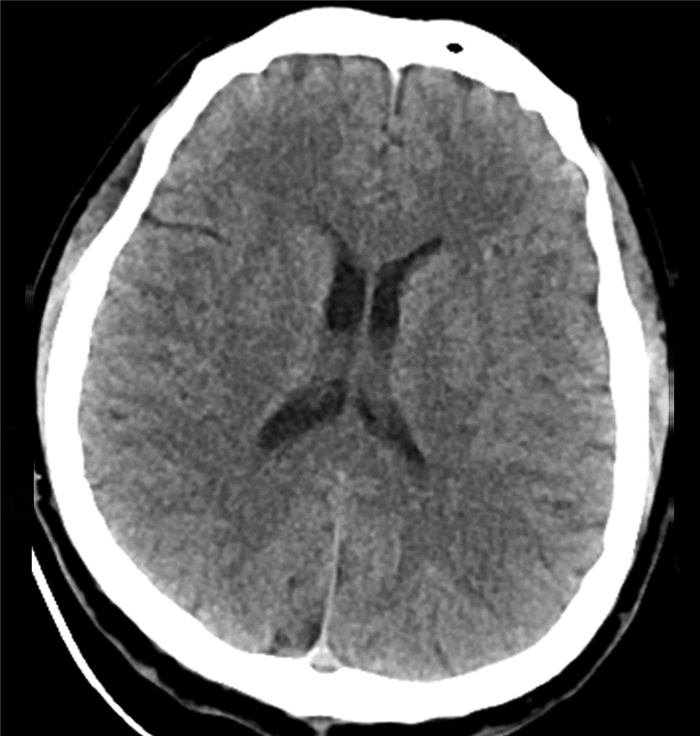

Endoscopic treatment of gastroesophageal varices complicated by posterior reversible encephalopathy syndrome: A case report

Tingting YU, Shanshan JIANG, Mengran ZHU, Yun BAI

2022, 38(1): 177-179. DOI: 10.3969/j.issn.1001-5256.2022.01.030

Abstract(830) HTML (198) PDF (3069KB)(60)

Abstract: